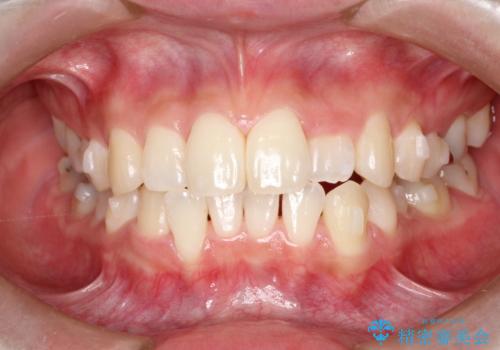

初診時の歯並びの状態としては、上下ともに前歯部の中等度のがたつきがあり、特に左上の前歯が1本内側に入り込んでしまっている状態でした。

また、2mm程度の正中離開がありました。